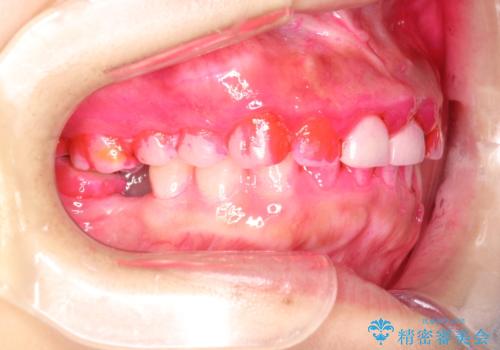

- 矯正治療のご相談で来院されました。歯科がかなり久々とのことでまずは、全体的なクリーニング希望とのことでした。

かなり久しぶりの歯科医院との事で、全体的に古くからの歯垢・歯石が多く付着していたため、自費クリーニング(PMTC)60分コース・歯周ポケット検査(保険適応)を行いました。

磨き残しが放置されると、そこで病原菌が繁殖し始めます。よって歯肉に炎症が生じ、歯周病の原因になることがあります。